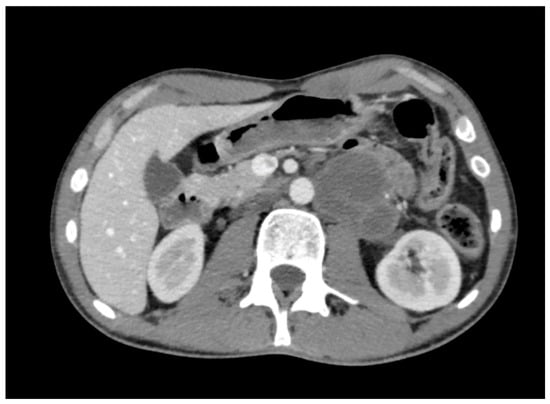

Ureteral and Vascular Events During Robotic Post-Chemotherapy Retroperitoneal Lymph Node Dissection: Technical Insights and Management Considerations

by Manuel Saavedra Centeno, Eduardo Albers Acosta, Clara Velasco Balanza, Lira Pelari Mici, Carlos Márquez Güemez, Marta Pérez Pérez, Ana Sánchez Ramírez and Luis Alberto San José Manso

Complications 2026, 3(1), 1; https://doi.org/10.3390/complications3010001 - 8 Jan 2026

Robotic retroperitoneal lymph node dissection (R-RPLND) represents an evolution in the surgical management of testicular germ cell tumors, offering reduced morbidity compared with open approaches. However, this procedure remains technically challenging, particularly after chemotherapy, due to dense fibrosis and distortion of the retroperitoneal [...] Read more.

Robotic retroperitoneal lymph node dissection (R-RPLND) represents an evolution in the surgical management of testicular germ cell tumors, offering reduced morbidity compared with open approaches. However, this procedure remains technically challenging, particularly after chemotherapy, due to dense fibrosis and distortion of the retroperitoneal anatomy. We report a case of an unrecognized intraoperative thermal injury causing a partial transection of the proximal ureter presenting postoperatively as a urinary fistula following R-RPLND for residual mass resection, along with a focused review of the contemporary literature on procedure-related complications. A review of large series highlights severe complications (Clavien–Dindo ≥ III) occurring in 6–12% of cases, with ureteral injuries occurring in up to 6%, often identified after surgery. This case underscores the importance of meticulous dissection, awareness of altered anatomy, and prompt intervention when unexpected events arise during R-RPLND. Full article

Show Figures